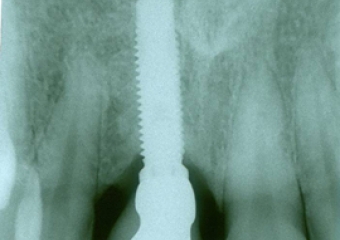

Raio X de controle realizado dia 01/04/2013

Imagens de 05 anos de controle, realizadas dia 01/04/2013